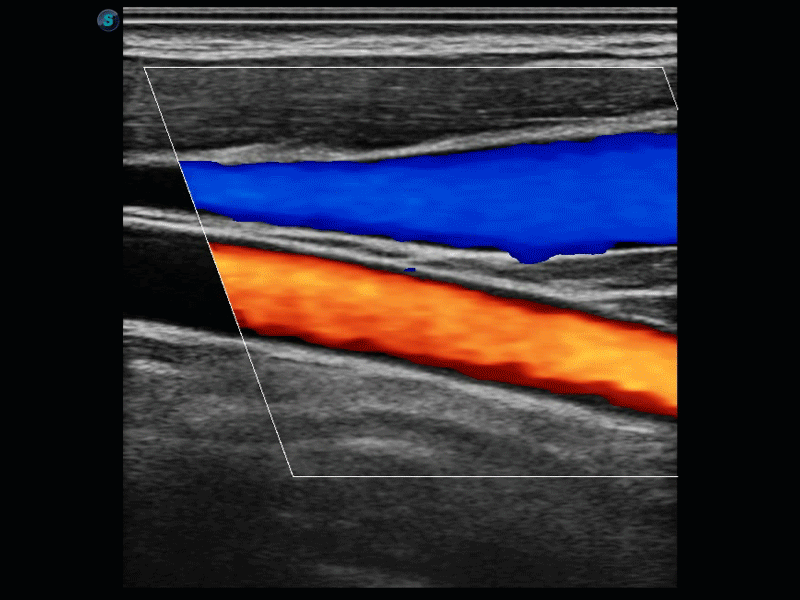

SR Flow高分辨率血流成像

高分辨率血流成像技术提高了对低速血流信号的检测能力。在提高空间分辨率的同时,也克服了血流外溢现象,为用户提供更加真实的血流动力学信息。

实时宽景成像技术

通过彩色血流和实时宽景相结合,可观察到完整的动静脉血流,方便医生检查。实时扫查过程中,如有任何操作失误也可以很容易地进行回扫擦除,而不会中断扫查。